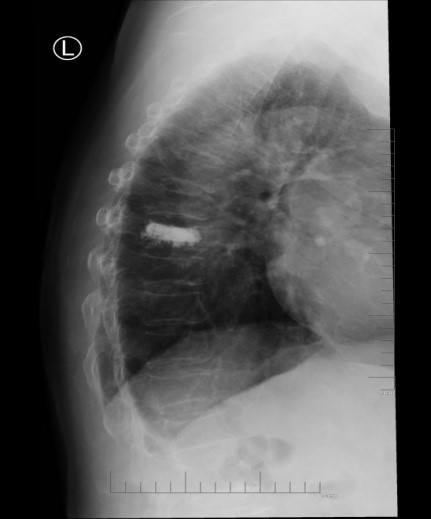

吴老太太今年86岁,同时患有心脏病、老慢支、哮喘、糖尿病等多种疾病,不久前因为并发心衰、呼衰在独墅湖医院经抢救后脱离危险。然而不巧的是,几天前自己在家只轻轻扭了一下腰,就感觉背部疼痛难忍,寝食难安。于是来到我院骨科就诊,医生怀疑是脊柱骨质疏松性骨折,安排收治住院,对病患进行磁共振检查后证实是“第8胸椎压缩性骨折”。

医生在诊断后决定行经皮椎体后突成形术(简称PKP术),需要病人在全身麻醉下俯卧位,医生在全程透视下完成手术。对于一般的患者来说不成问题,而对吴老太太而言却难以实施。首先,她的全身情况较差,心肺功能不全,基础疾病多且严重。入院时就有明显的呼吸困难,氧饱和度只有70%左右,很难耐受全身麻醉。即使勉强度过手术阶段,术后也可能要气管插管,靠呼吸机维持生命,肺部感染则难以控制。其次,如果采用局部麻醉俯卧位手术,尽管可以规避全麻的风险,但该患者根本不能承受俯卧位对心肺功能的影响。但如果不采取手术,卧床以及日夜不停的疼痛对已经遭受过心衰和呼衰的吴老太太来说是雪上加霜。

在与家属充分沟通后,3月11日上午,骨科姜为民主任亲自披挂上阵,杨小海主任医师等团队成员紧密配合,一切按计划进行。然而,刚开始消毒,预料中的问题出现了:患者开始扭动身体,又无法有效沟通,如此手术将难以继续下去。好在姜主任团队早有预案:静脉适量给药镇静。在麻醉科侯永恒副主任的密切配合下,患者恢复了平静,各项生命指标平稳。姜主任凭借高超的手术技巧,仅用25分钟即高质量地完成了这例非常规手术。